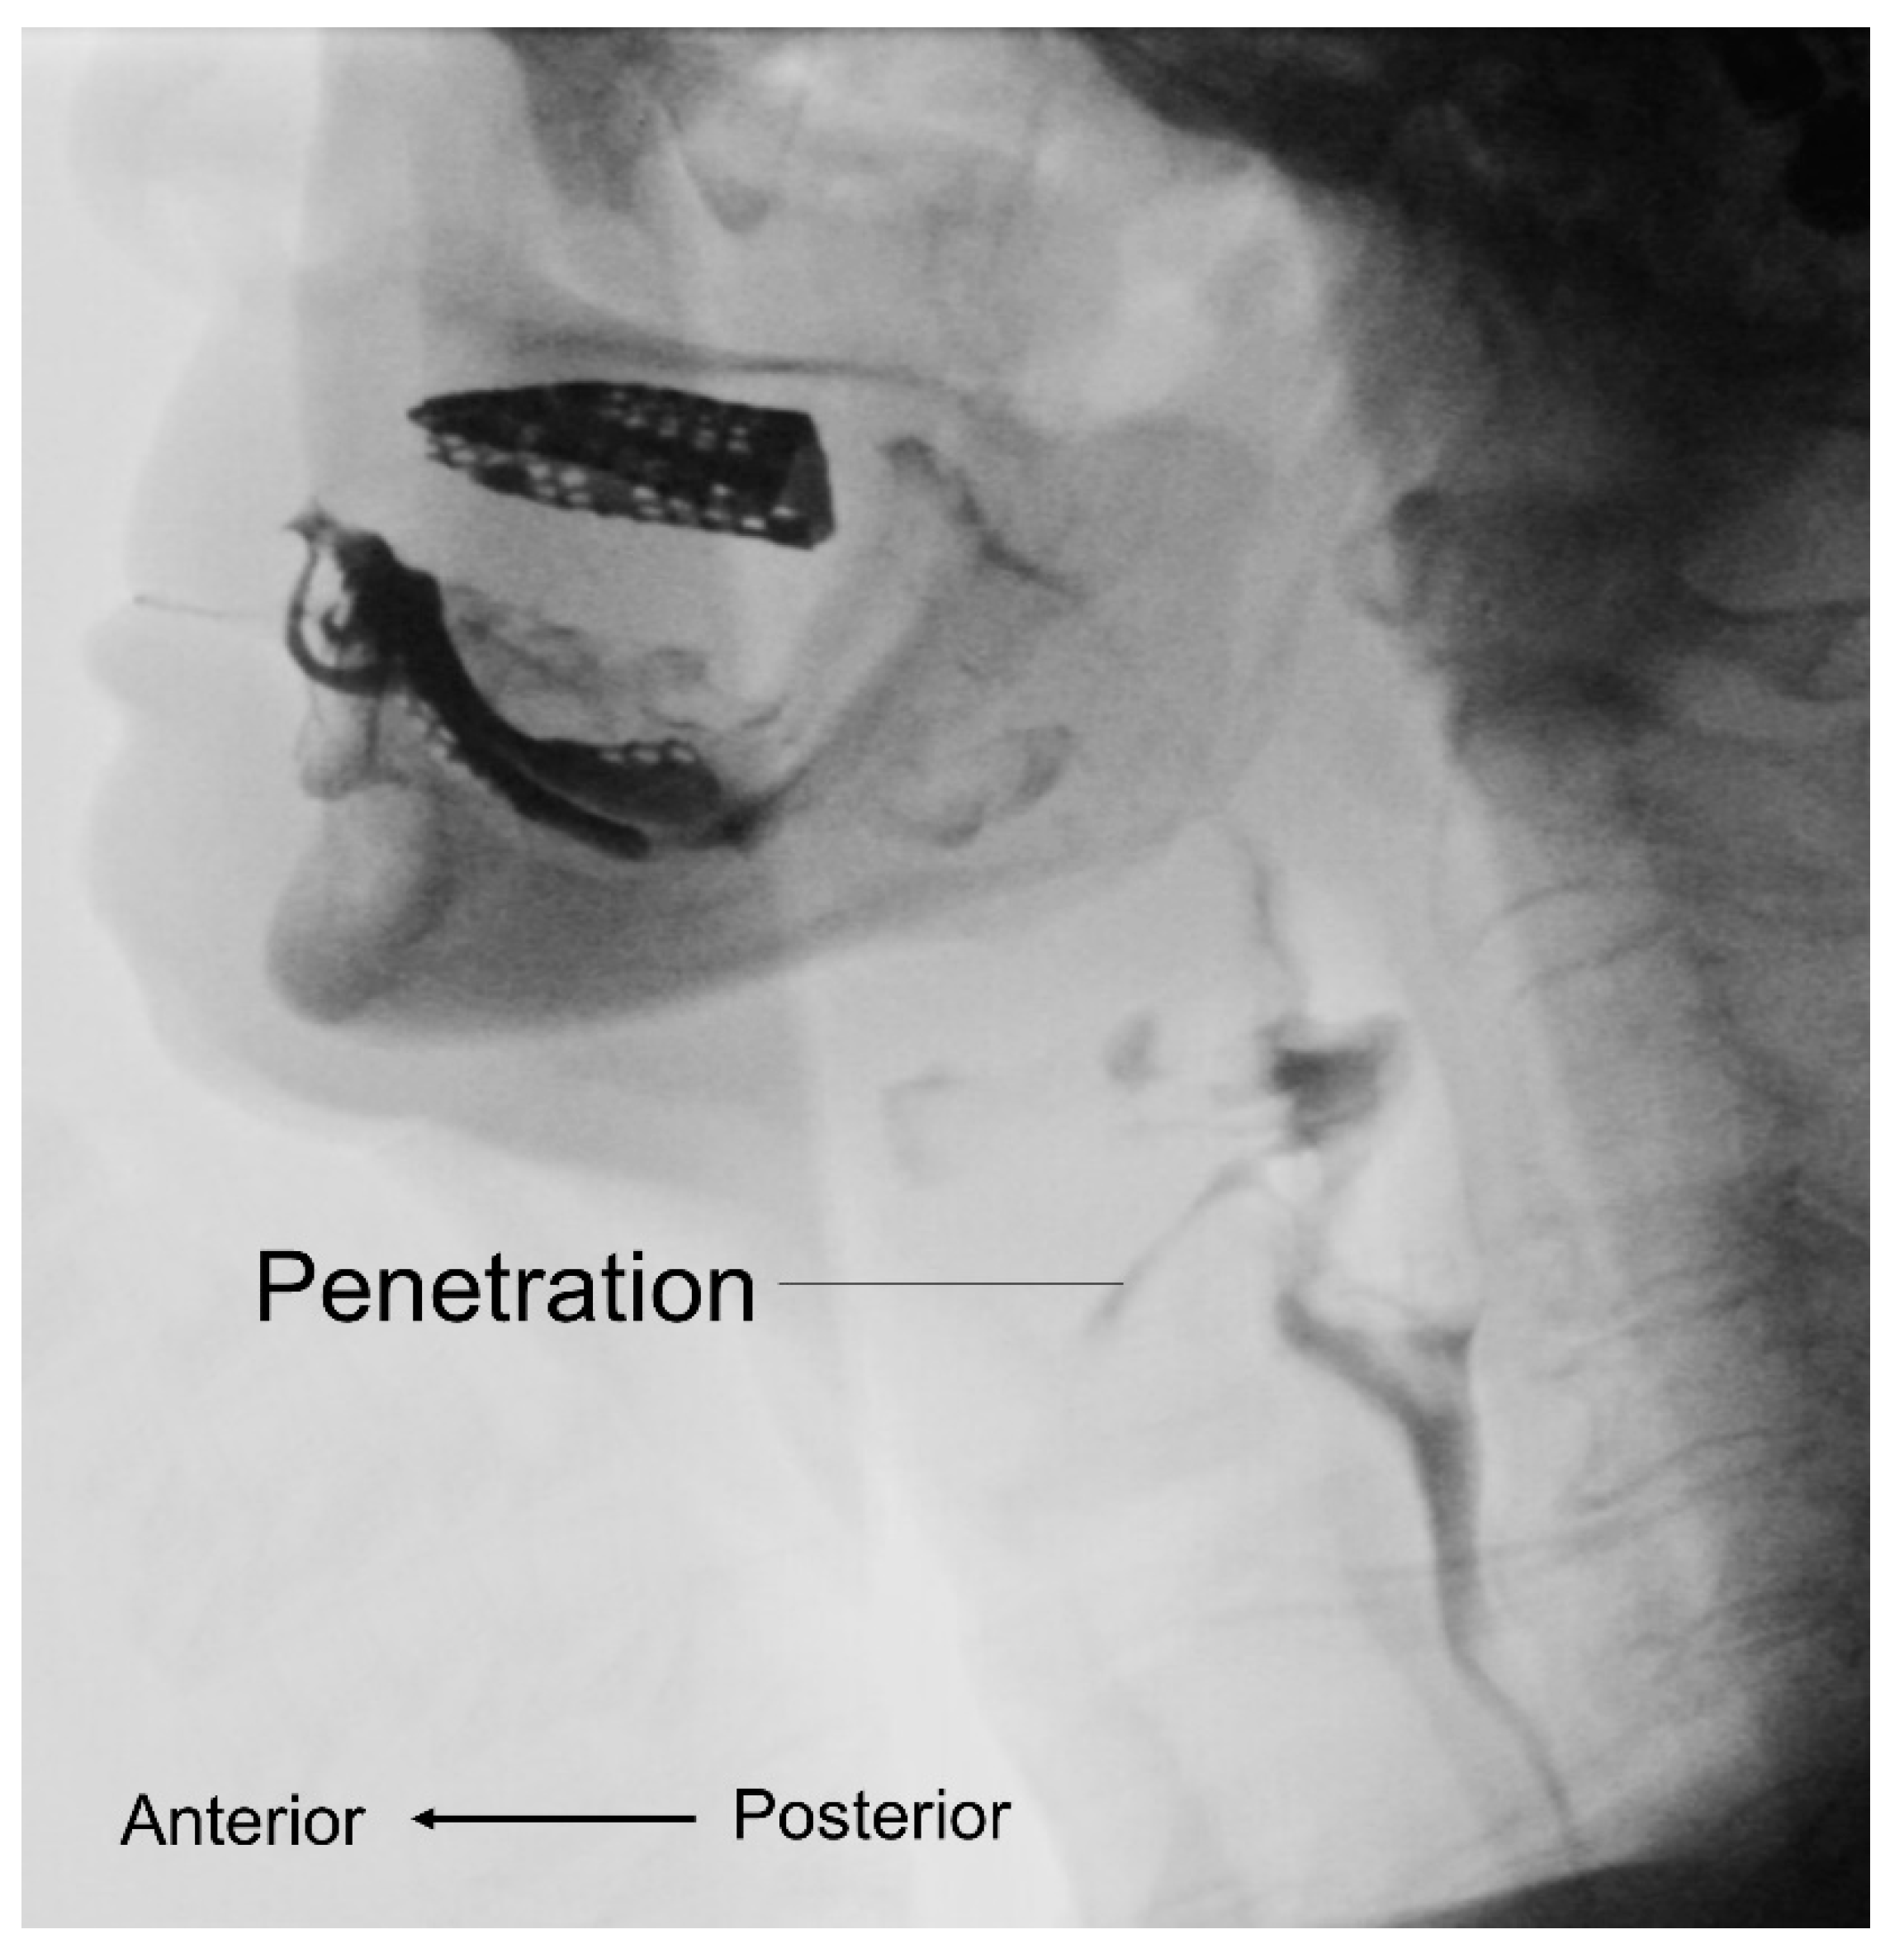

3.3. Videofluoroscopic Swallow Study

- Miyashita, T.; Kikutani, T.; Nagashima, K.; Igarashi, K.; Tamura, F. The effects of sarcopenic dysphagia on the dynamics of swallowing organs observed on videofluoroscopic swallowing studies. J. Oral Rehabil. 2020, 47, 584–590. [Google Scholar] [CrossRef]